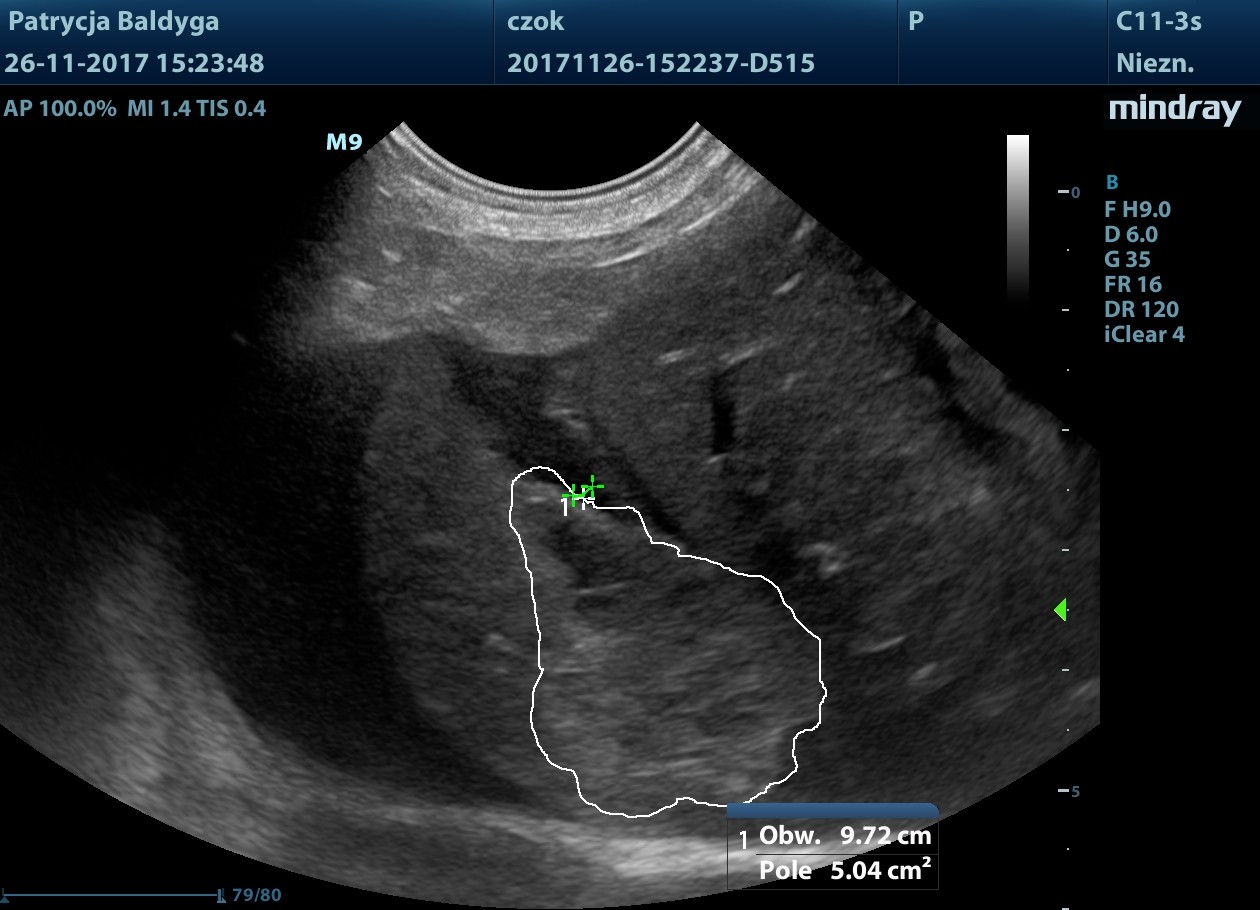

Miąższ szczególnie płatów lewych o miejscowo wzmożonej echogeniczności, nieco nieregularnej torebce, z obecnością zmiany ogniskowej najpewniej krwiaka pourazowego ok. 3,2 x 1,6 cm w płacie lewym bocznym modulującego znacznie torebkę powierzchni trzewnej.

Obecność znacznie zwiększonych ilości wolnego, nieco zagęszczonego płynu w jamie otrzewnej, widocznego w dużej ilości przypęcherzowo, przywątrobowo, pomiędzy pętlami jelit oraz śladowo również w przestrzeni zaotrzewnowej

- co nasuwa duże podejrzenie krwotoku masywnego, najpewniej z wątroby, wskazanie do laparotomii zwiadowczej.